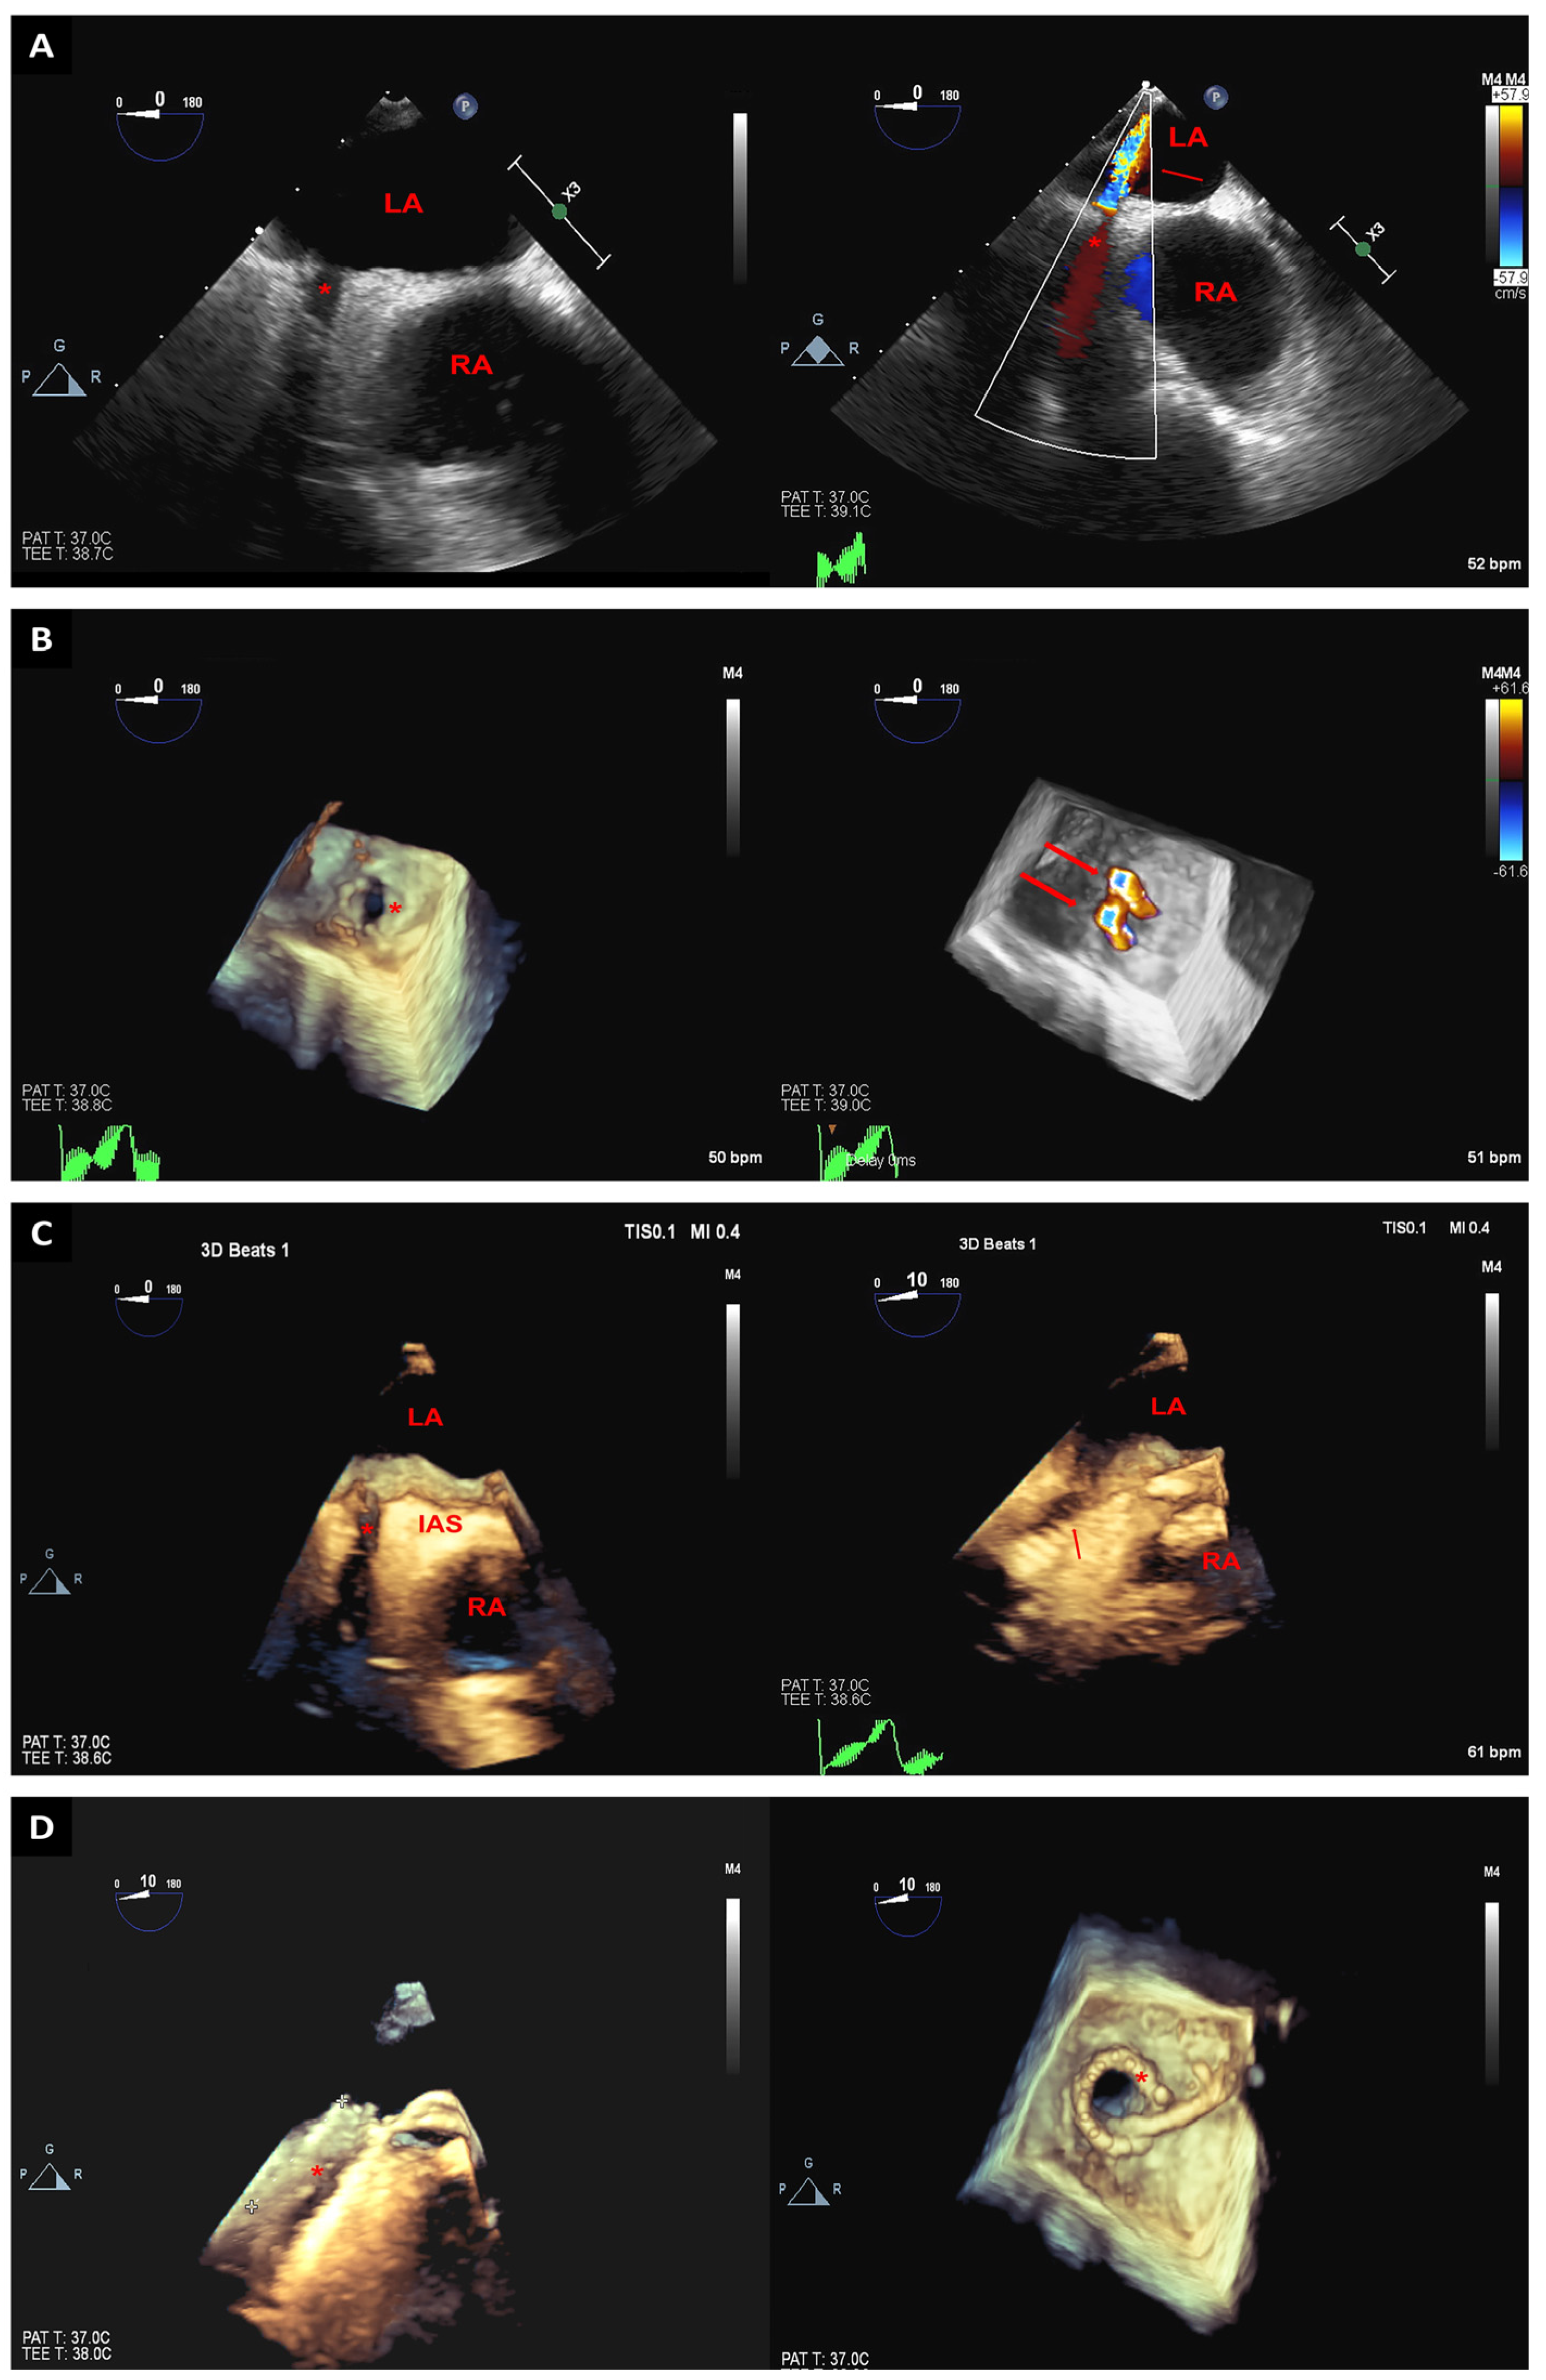

2. Trans-Septal Puncture